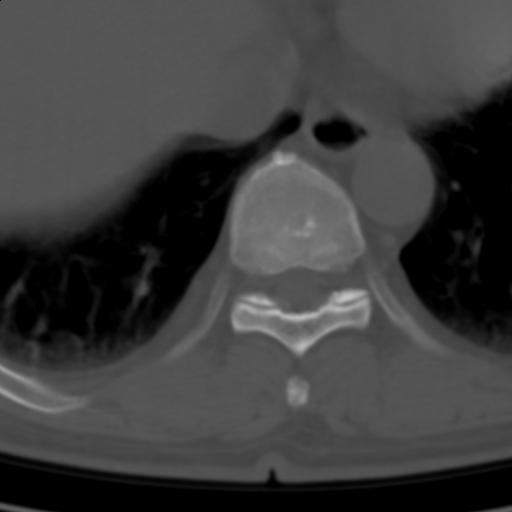

标题: CT25189:胸椎ct,请会诊!

既往食管癌,现行ct检查!

中上段食道癌,椎体轻度退变。

椎体退行性改变,食管癌。

支持中上段食道癌,椎体轻度退变,必要时做ect。